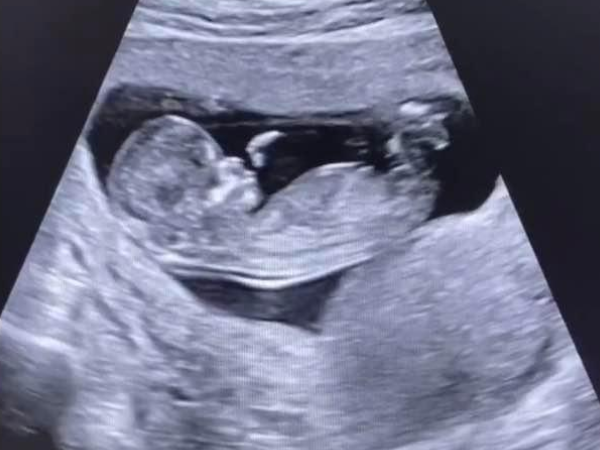

那么如果怀孕60天未见胚芽正常吗,怀孕初期,孕妈妈的关注度放在胎儿的发育上,在怀孕一个多月时想知道上面时候能看到胚芽,检查看到胚芽之后担心胚芽发育不正常,怀孕7周..